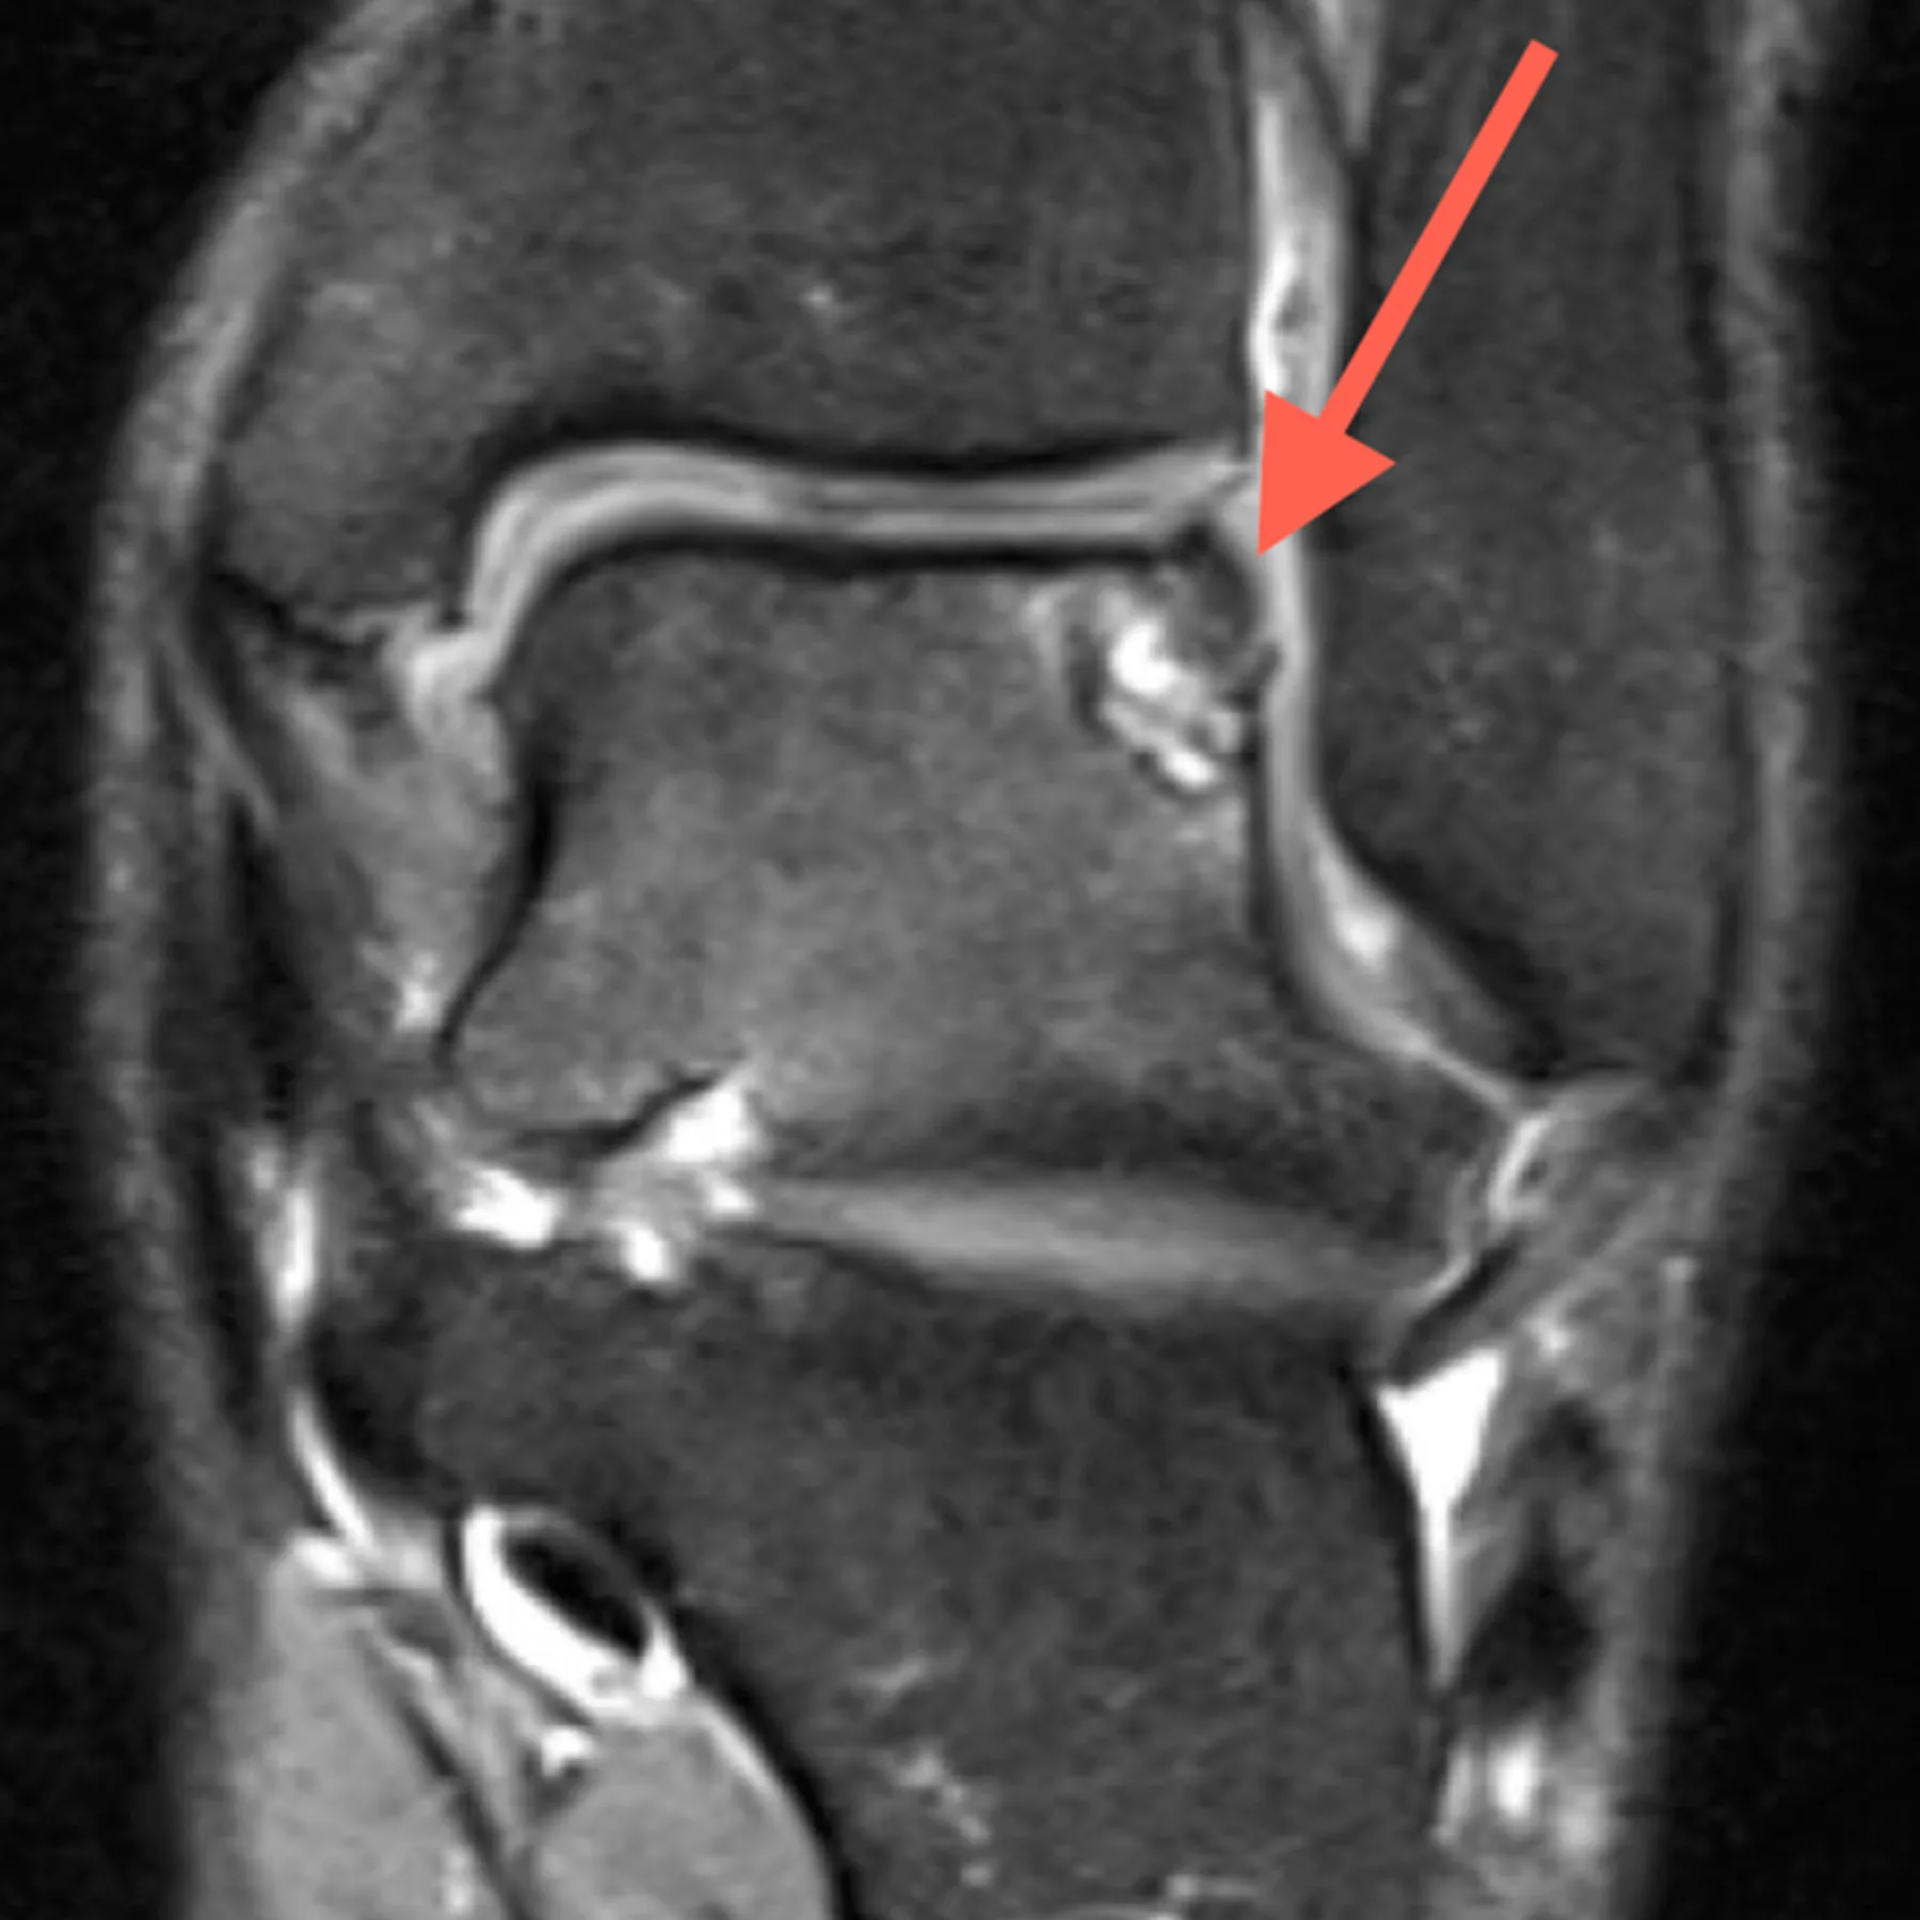

Diagnóstico Preciso: El Mapa de tu Recuperación

Todo comienza con una evaluación exhaustiva.

Te escucharemos atentamente para conocer tu historia y realizaremos un examen físico detallado:

- Valoración de la movilidad: Mediremos los rangos de movimiento de tu tobillo para ver qué gestos están limitados.

- Pruebas de estabilidad: Con maniobras específicas, evaluaremos la integridad de tus ligamentos.

- Análisis de la marcha y la pisada: Observaremos cómo caminas para detectar posibles desequilibrios.

- Ecografía musculoesquelética: Si es necesario, utilizamos la ecografía en la propia consulta para ver en tiempo real el estado de tus tendones y ligamentos, obteniendo un diagnóstico certero al instante.